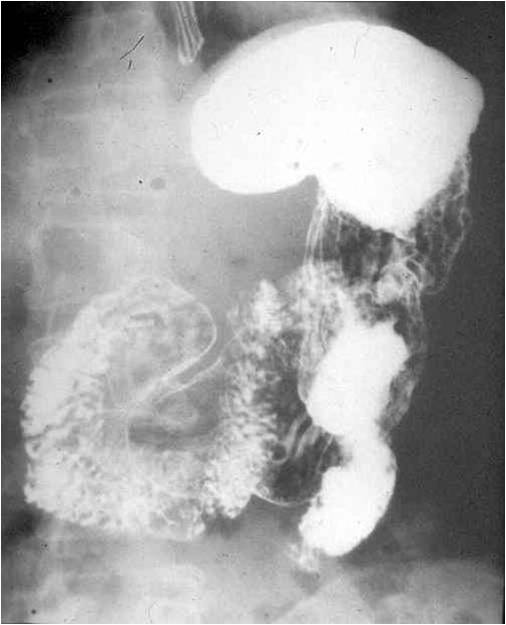

Image

Fig.21.: Radiograph of selective enterocylsis